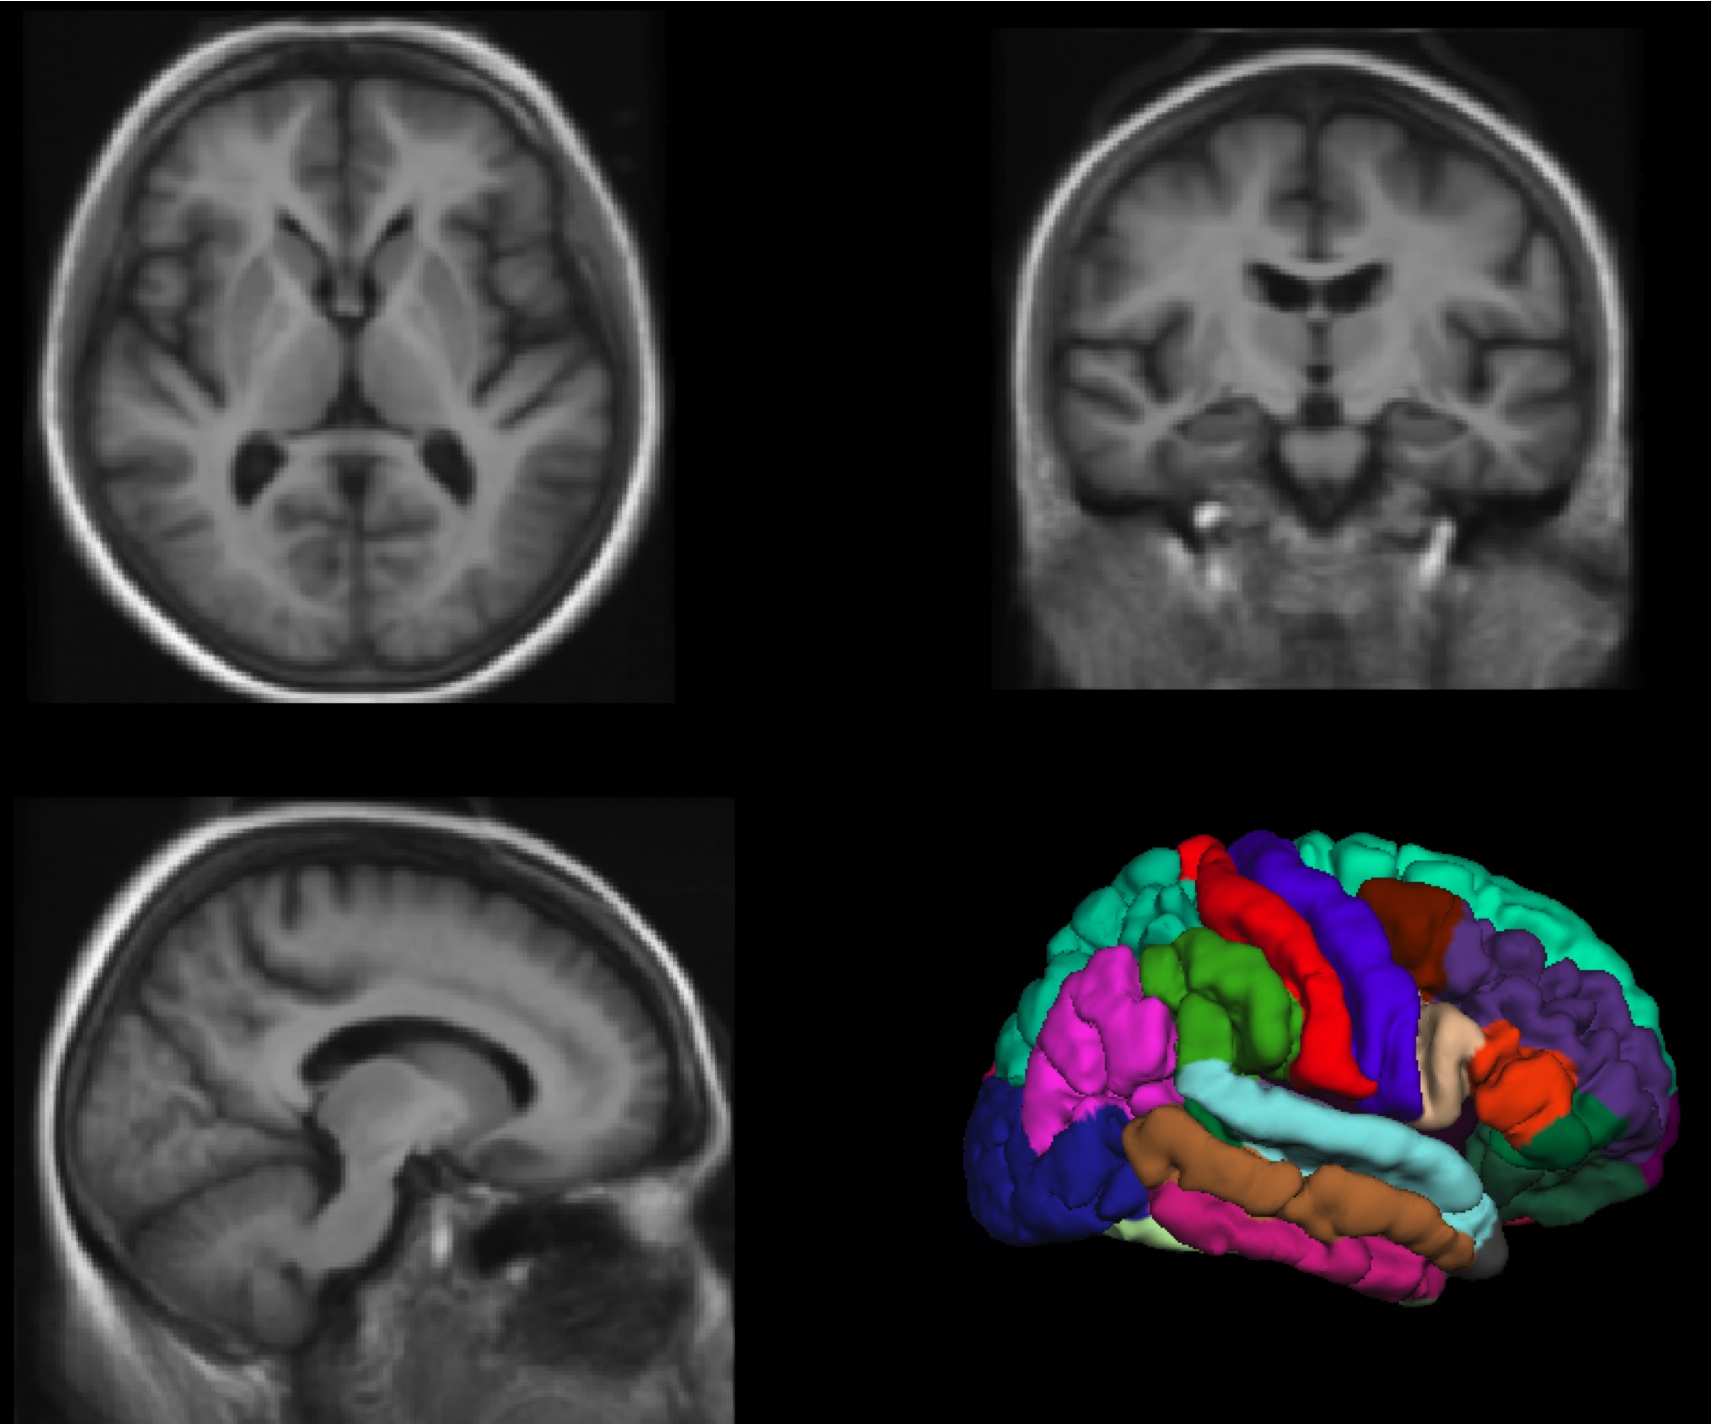

We are working on methods for constructing average brain atlases using large deformation image registration. Current volume-based brain atlases have difficulty representing the complex and convoluted folding patterns of the cerebral cortex; using multi-structure whole brain registration we can account for much of the inter-subject variability and represent the average cortical and subcortical features much more accurately.

Multi-structure whole brain registration and population average

Accepted in IEEE Engineering in Medicine and Biology Conference (EMBC 2009) (Paper No.: 2182).